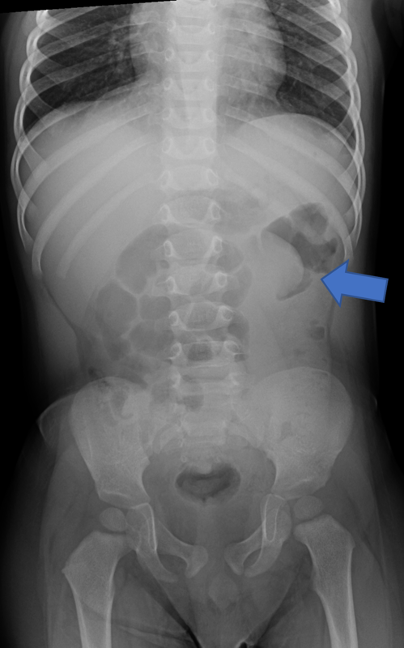

Diagnosis of intussusception is made primarily through imaging, in the setting of the above clinical presentation. Often abdominal radiographs are obtained as the first image in the emergency department setting. Radiographs are neither sensitive nor specific, but are useful for identification of an obstructive bowel gas pattern and the presence of abdominal free air.3,4 The primary signs to look for when examining an abdominal radiograph are the “crescent sign,” which is formed by bowel gas delineating the vertex of the intussusception and a lack of bowel gas in the ascending colon (Fig. 1).3 Ultrasound (US) is a highly sensitive modality for the identification of intussusception and is the preferred means of diagnosis in pediatric populations.1,3,4

(Figure 1: left) (Figure 2: Right)

Figure 1: Supine abdominal radiograph. A crescent sign is demonstrated near the splenic flexure. There is mild gaseous distention of the proximal bowel, with paucity of gas in the left abdomen.